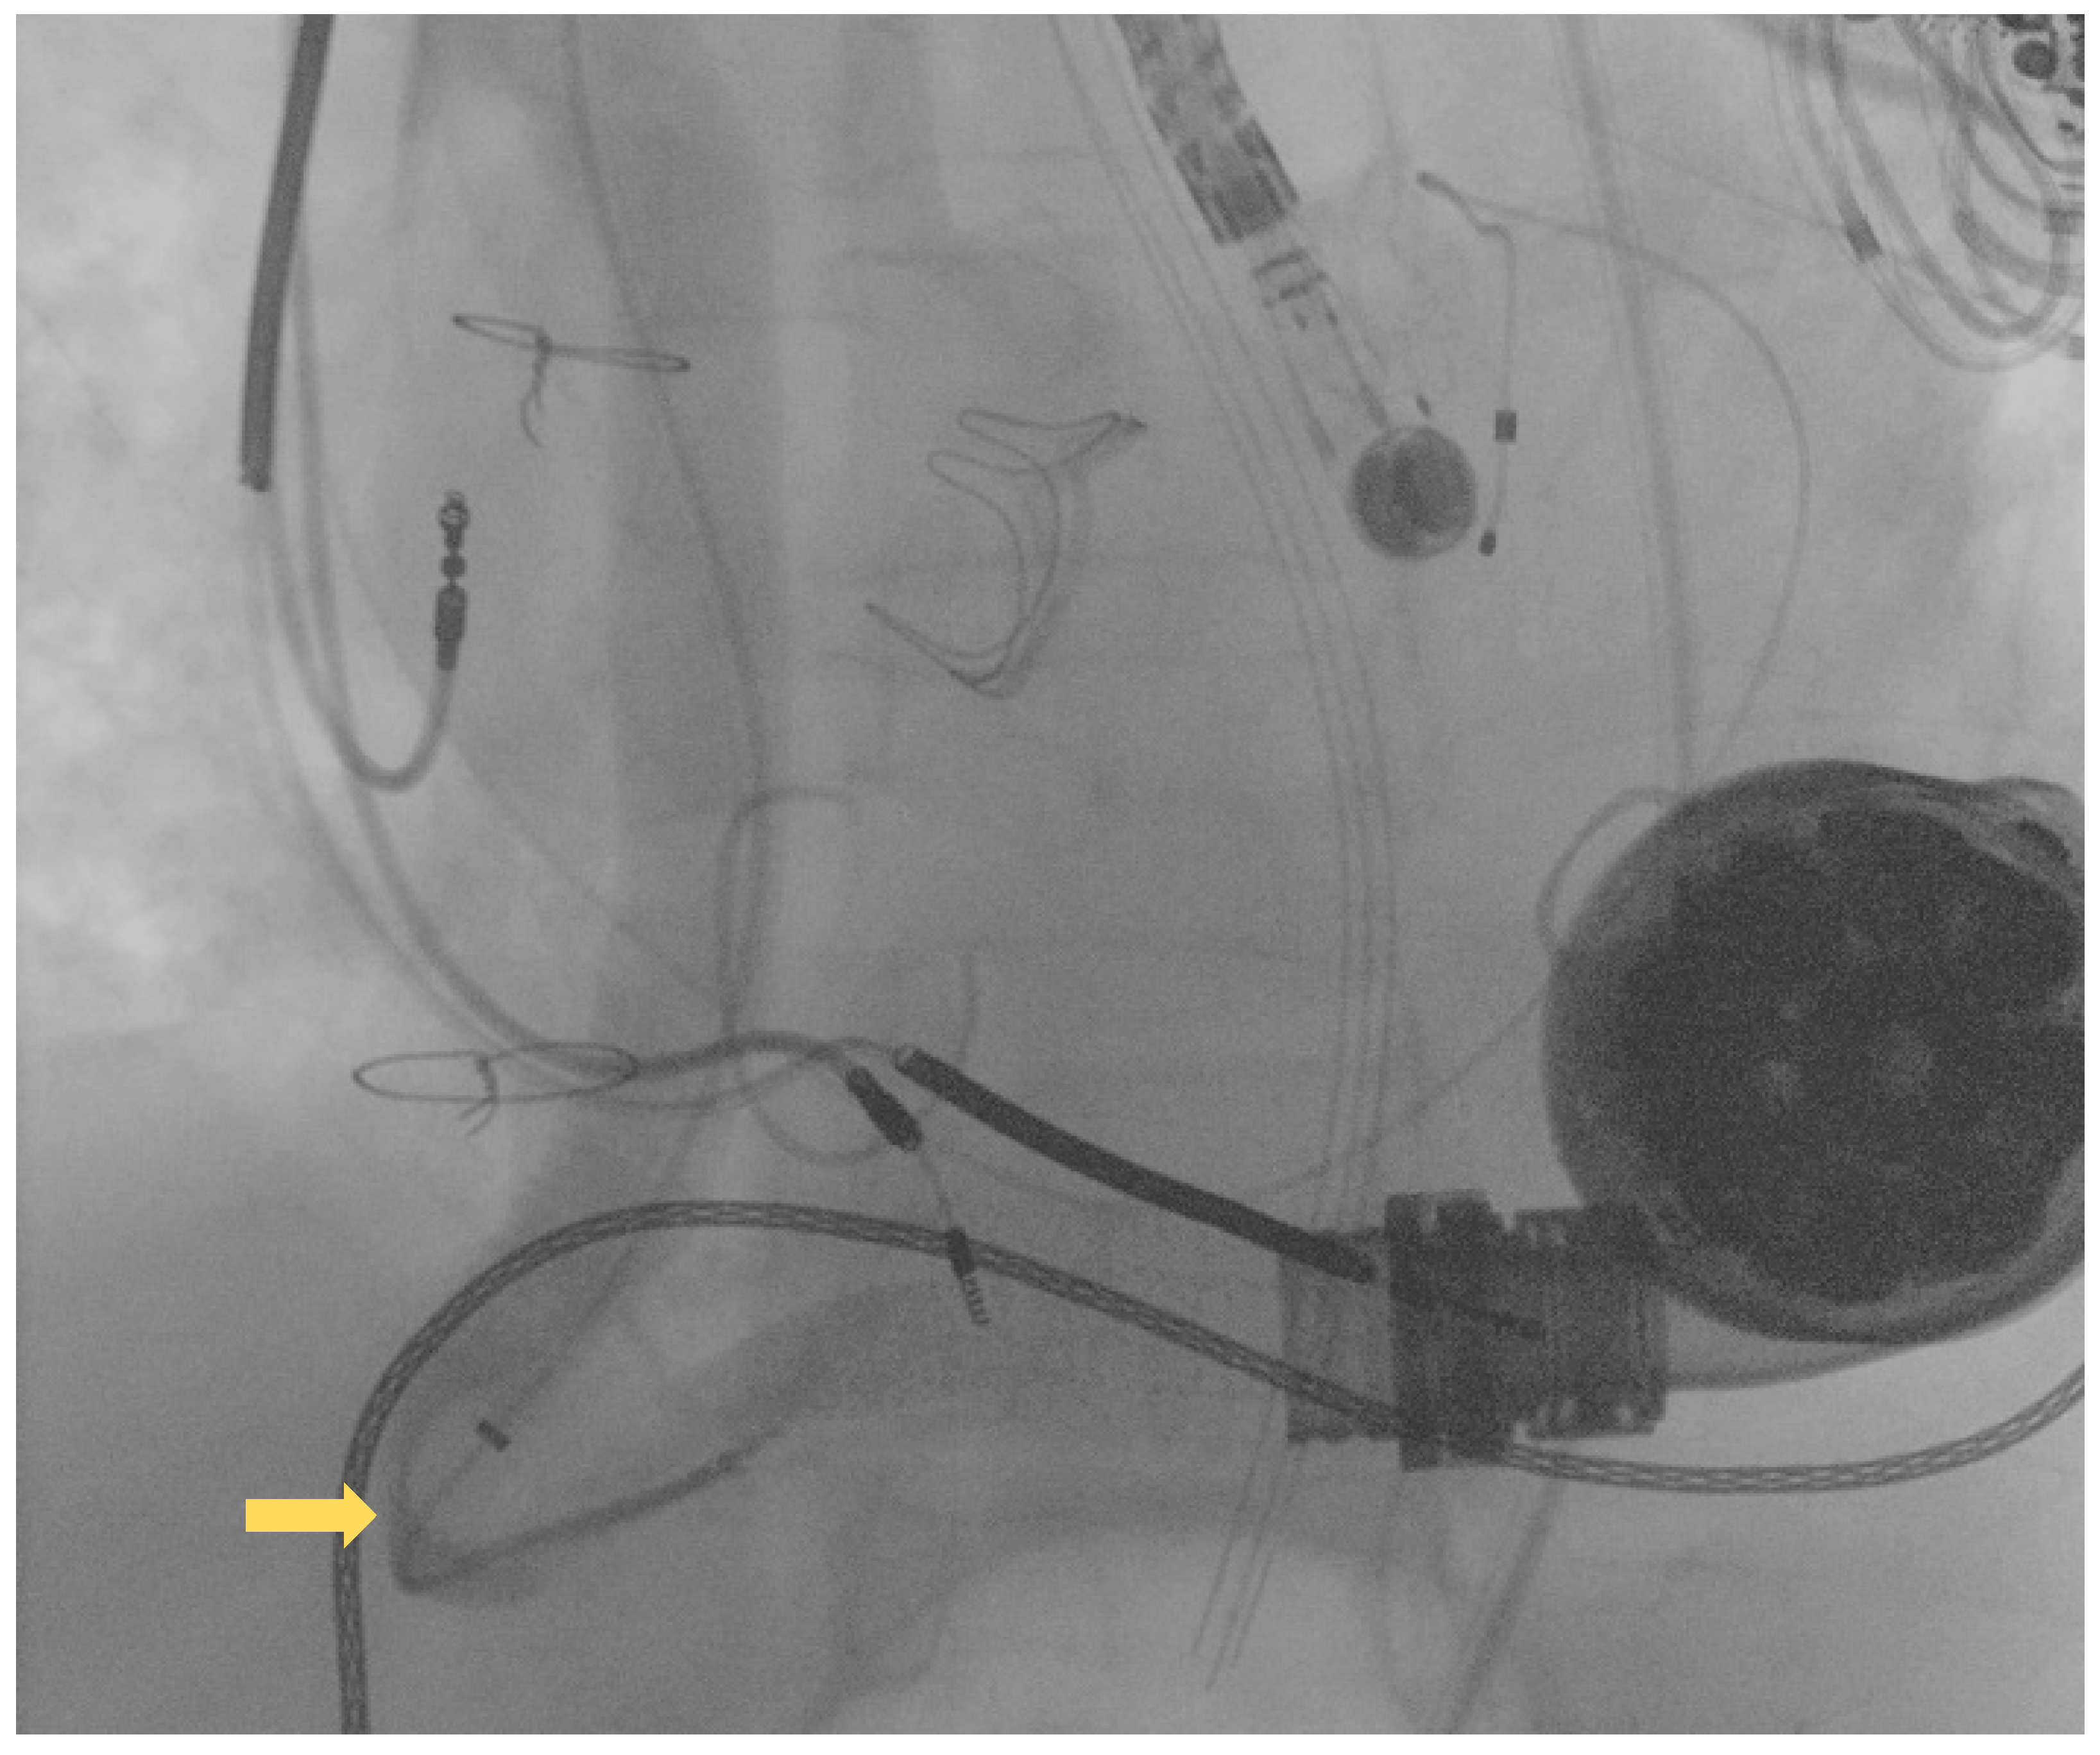

Following this first LVAD intervention, a dual antithrombotic regimen with aspirin and a vitamin K antagonist (VKA) was administered. However, antiplatelet therapy was suspended few months after due to a major neurological bleeding. At admission, the patient showed unstable clinical conditions (systemic blood pressure of 90/60 mmHg, a heart rate of 130 beats per minute, a respiratory rate of 20 breaths per minute, arterial oxygen saturation of 85%). Laboratory markers showed elevated serum lactate and impaired renal function, without signs of ongoing hemolysis. Due to the impeding cardiogenic shock, the patient was admitted to intensive care unit (ICU). Echocardiographic evaluation confirmed the presence of severe LV dysfunction (ejection fraction < 25%) and dilation. Moreover, severe right ventricular (RV) dysfunction (TAPSE < 15 mm) was found. LVAD logged several low-flow alarms (1.5 L/min, 8000 rpm), suggesting that a major device failure could be the trigger of this condition. Considering the unstable clinical setting and the past medical history of OGO [8], computed tomography (CT) was deferred and the patient was directly transferred to the catheterization laboratory to perform an urgent invasive diagnostic assessment. The procedure was performed under general anesthesia and with continuous transesophageal echocardiography monitoring. In order to avoid possible circulatory collapse during the procedure, both the arterial and venous femoral accesses were surgically obtained with the purpose of rapidly deploying veno-arterial extracorporeal membrane oxygenation (ECMO) assistance, if necessary. Via the right femoral artery, a first attempt at performing angiography using a diagnostic pig-tail catheter failed. Considered the presence of a known kinking site [8], an 8F 110 cm-long sheet (Flexor®Ansel Guiding Sheath, Cook Medical, Bloomington, IN, USA) was conducted through the distal anastomosis of the outflow graft to provide further support. Following this, a 130 cm-long supporting catheter (TrailBlazer™, Medtronic) over standard 0.035″ × 260 cm hydrophilic guidewire was advanced beyond the kinking and a diagnostic angiography was performed. As showed in Figure 2, a discrete filling defect located at the kinking site was found, suggesting recurrent thrombosis.

Figure 2.

Diagnostic angiography showing recurrent outflow graft obstruction (yellow arrow).